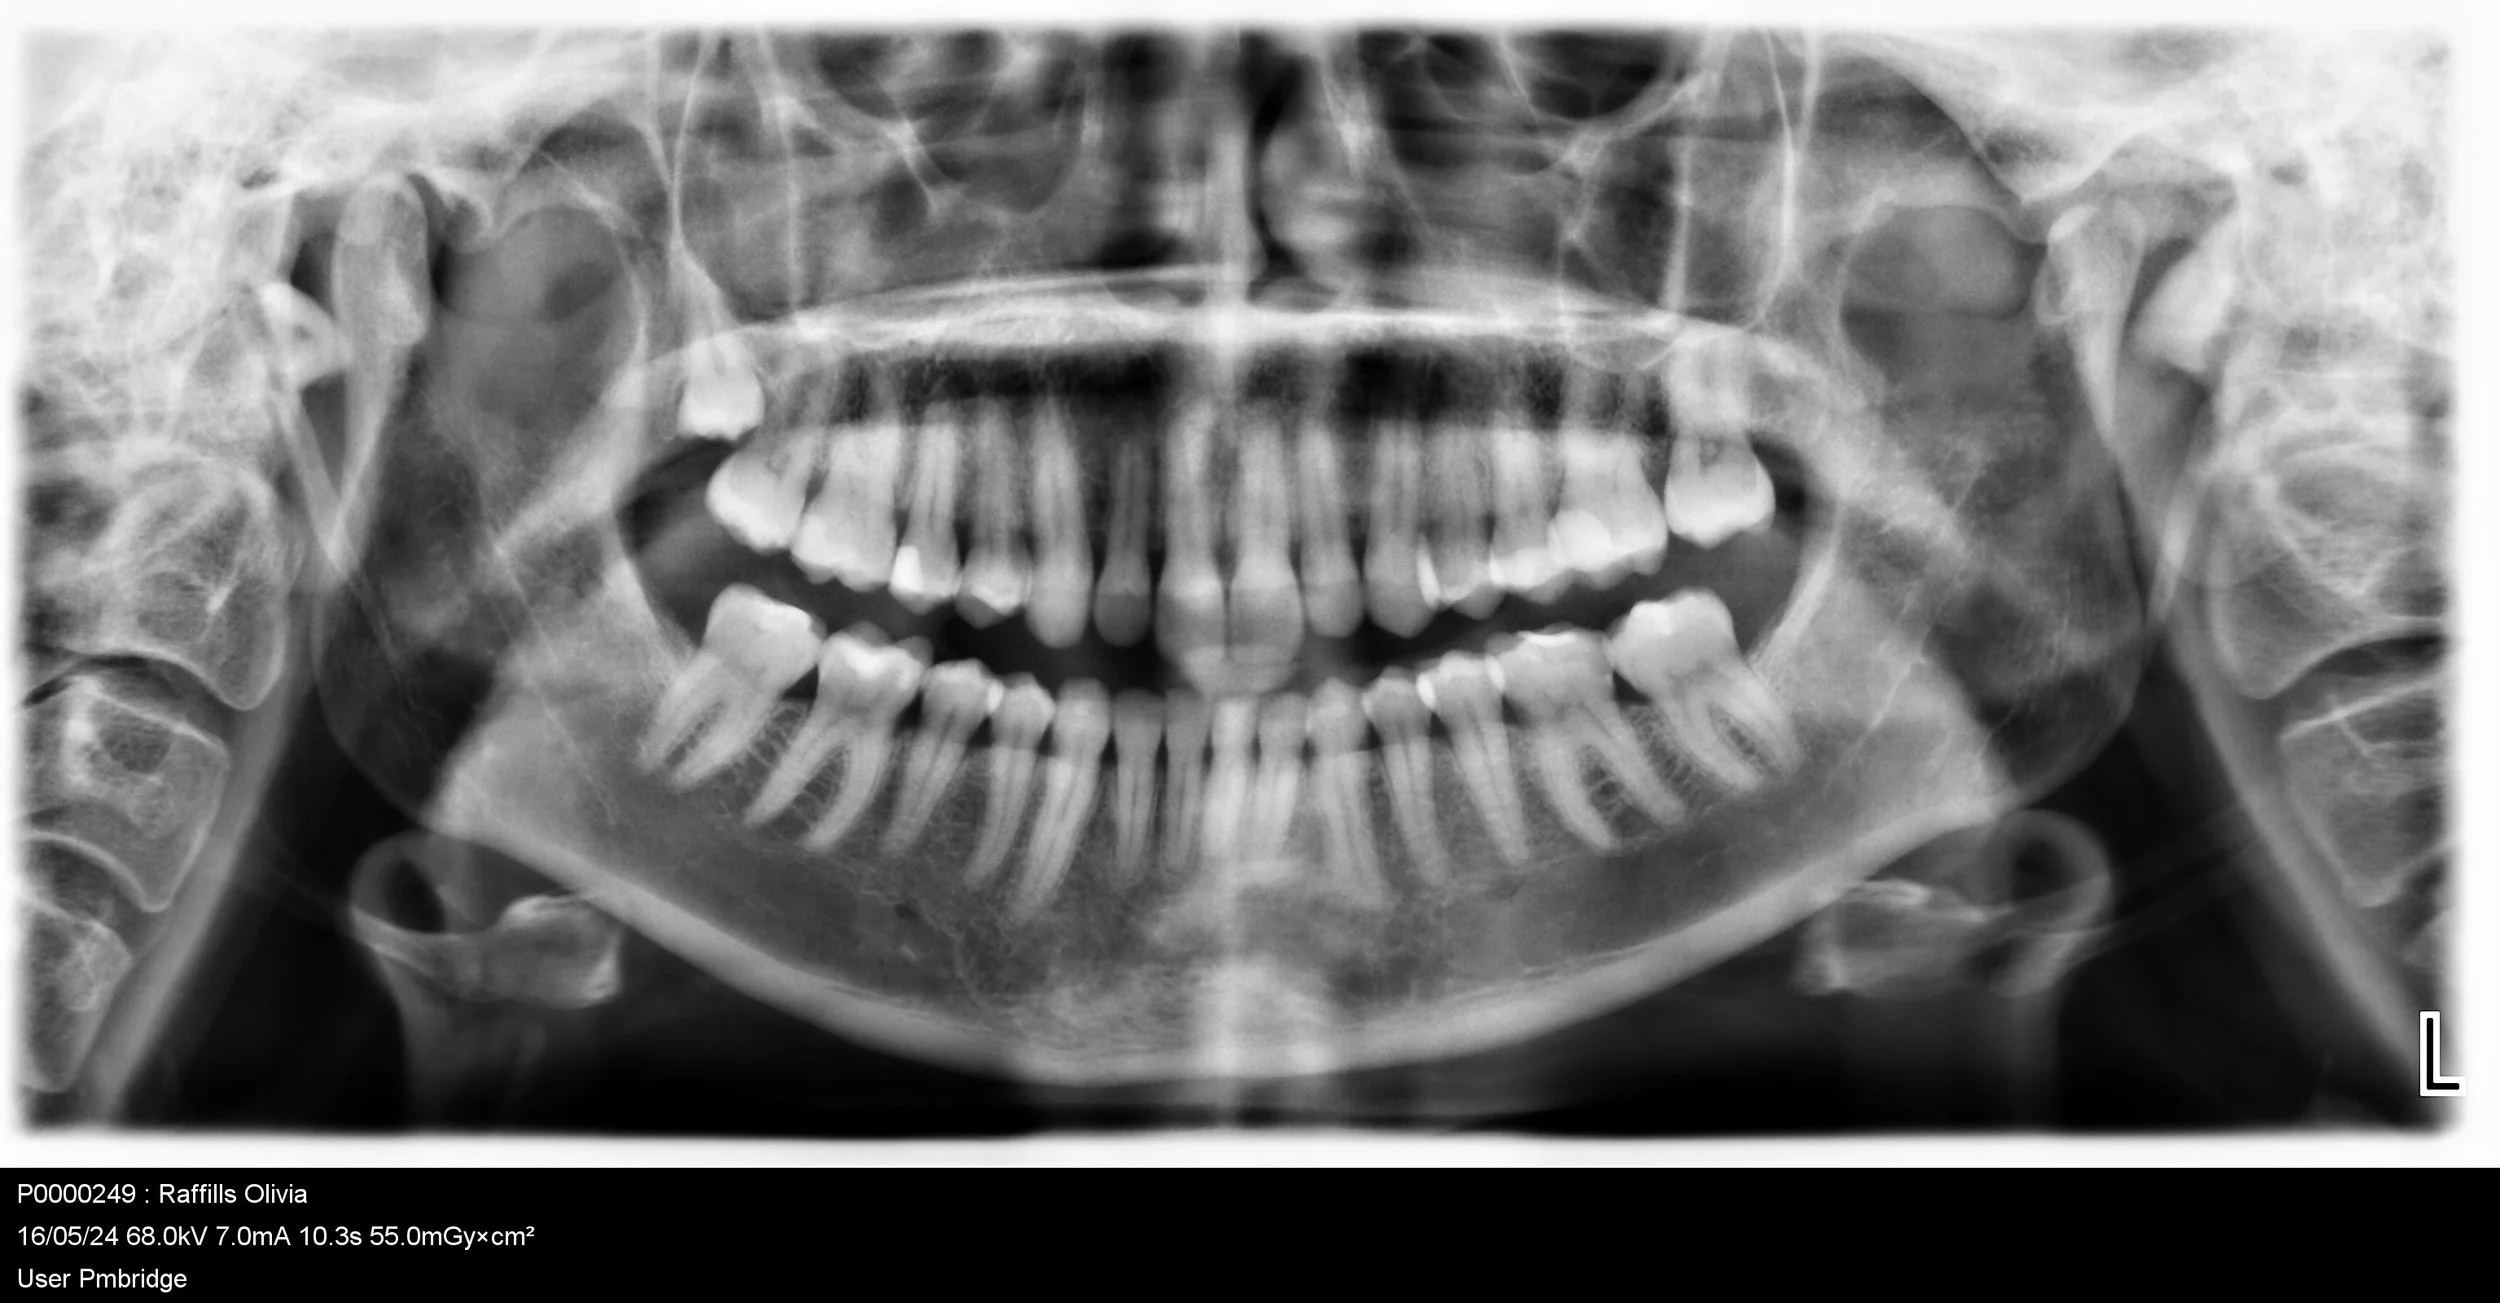

OPG

An OPG, also known as a panoramic X-ray, is a dental X-ray that offers a panoramic view of the teeth, mouth, and jaws.

An OPG, also known as a panoramic X-ray, is a dental X-ray that offers a panoramic view of the teeth, mouth, and jaws. This comfortable and non-invasive test involves the patient biting down on a small piece of plastic while the OPG machine rotates around their head to capture a two-dimensional image from ear to ear. This valuable diagnostic tool helps dentists identify various dental and oral health issues.